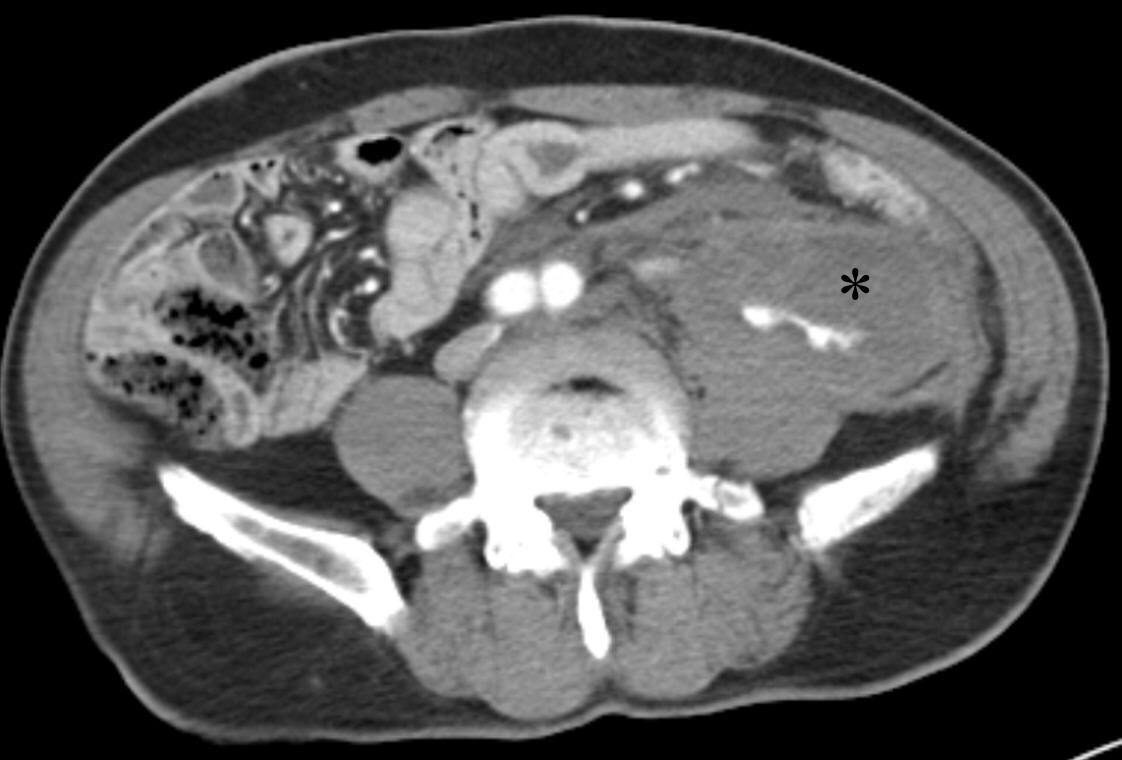

- Review Article Mar 23, 2026 Clinical challenges and transjugular intrahepatic portosystemic shunt strategies for pyrrolizidine alkaloid-induced hepatic sinusoidal obstruction syndrome: an Asian perspective Tan-Yang Zhou, Hong-Liang Wang, Zhi-Cheng Jin, et al. Korean J Interv Radiol 2026;31(1):24-35.